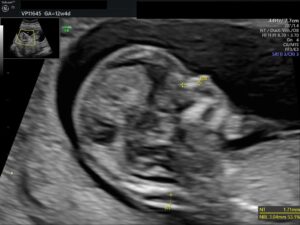

12.- 14. SSW

zertifiziert nach FMF London

• frühe Feindiagnostik: ausführliche Ultraschalluntersuchung zum Erkennen schwerer  fetaler Organfehlbildungen

• Nackenfaltenmessung (inklusive Zusatzmarker: Messung Nasenbein, Fluss über der  Trikuspidalklappe, Fluss im Ductus venosus) per Ultraschall zur Risikoberechnung  Trisomie 13,18, 21